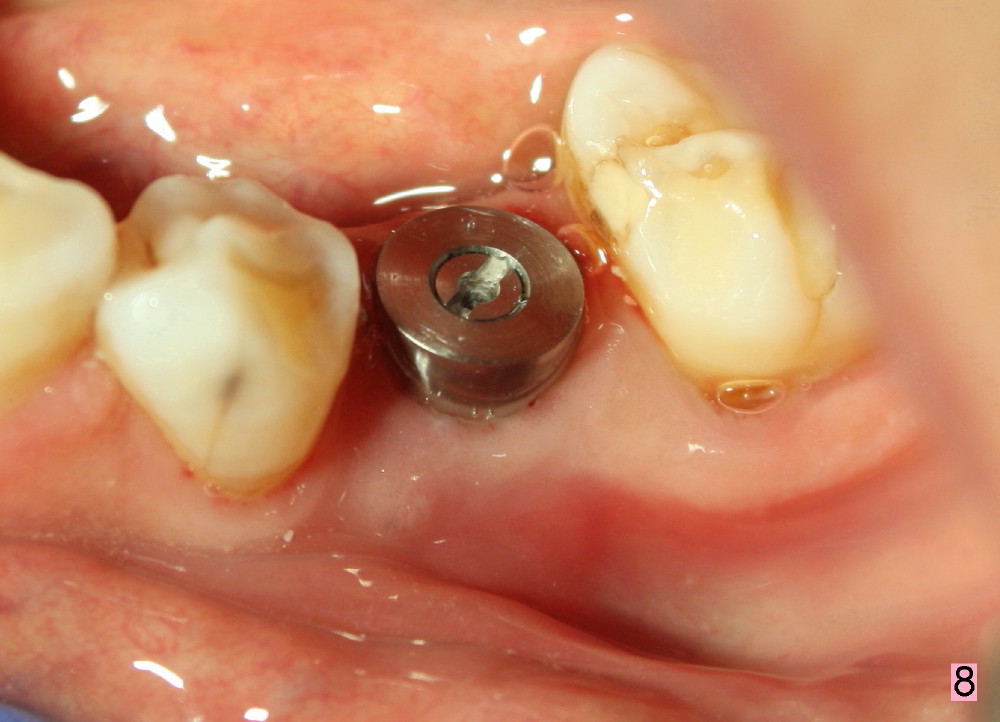

Taking multiple intraop X-ray is also necessary for depth adjustment (Fig.3-5).  For example, when a 5x20 mm tap is inserted at the depth of 17 mm, it is close to the mental loop (Fig.4), whereas the binding to the bone is minimal.  So a larger implant is to be placed at a shallower depth (Fig.5: 6x17 mm with insertion torque >60 Ncm).  The shallower implant placement creates limited space for future abutment and crown (Fig.6,7).  A short abutment will be used and the implant margin will be prepared as low as possible.  As expected, the wound heals in a week (Fig.8).

Six months postop, bone density around the implant increases (Fig.9).  There is slight gingival recession buccal to the implant (Fig.10 arrow).  A short abutment is placed and prepared short (Fig.11 A); the margin is prepared as low as possible in the implant (I).

When the crown is bonded, the papillae (*) look basically normal lingually (Fig.12) and buccally (Fig.13).